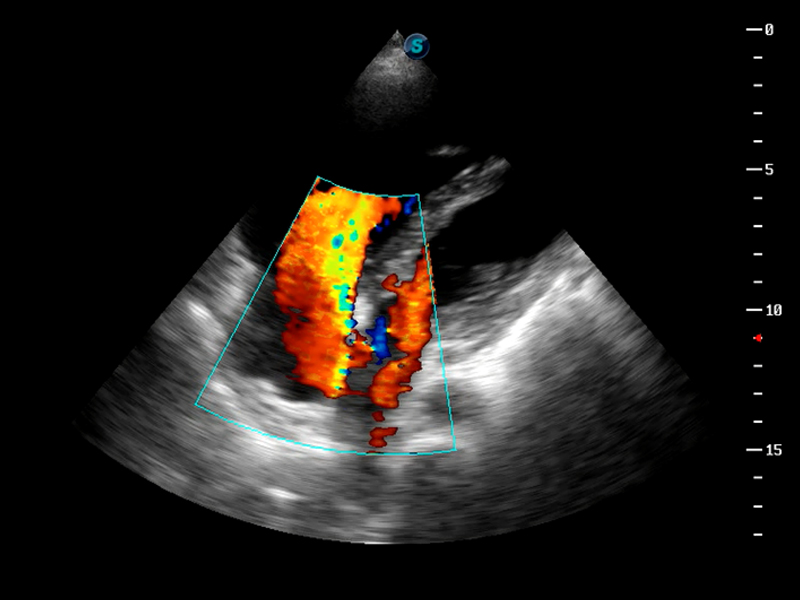

S9便携式彩色多普勒超声诊断仪是云顶集团官网研发的高端便携彩超设备,外观设计新颖、产品性能卓越。S9在便携超声领域采用了突破传统的触摸屏交互设计,并以先进的软件硬件技术和设计理念,为您带来清晰的图像质量、稳定的工作性能和便捷的操作体验。

TDI组织多普勒成像